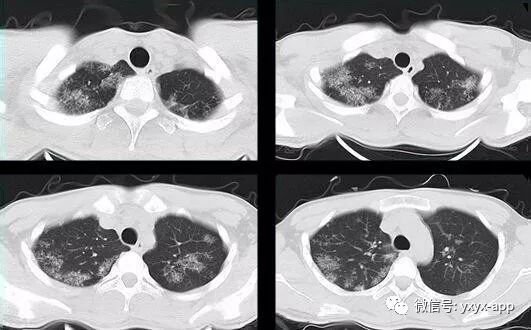

评论:两肺斑片状磨玻璃影,与周围组织分界清楚,呈“地图样”表现,部分病变延伸至胸膜下,部分小叶间隔增厚,气管居中,肺门及纵膈未见肿大淋巴结影,未见胸腔积液。患者青年男性,临床症状轻微影像表现严重,抗炎治疗无效。考虑肺泡蛋白沉积症

1、两肺较淡的斑片状磨玻璃影,不呈叶段分布,病变可延伸至胸膜下,其中磨玻璃影中可见小结节影,磨玻璃影与正常肺组织分界清楚,形成“地图样”改变,这种地图样分布的原因,可能是由于这种斑片影以肺小叶为病变单位,小叶间隔在一定程度上限制了病变的蔓延;

2、由于小叶间隔和小叶内间隔的增厚形成网格状阴影改变,弥漫的磨玻璃影及其内部的网格小叶间隔增厚形成了“铺路石样”改变;

3、实变区具有多样性,多种不同程度的病变共存,病灶内可见支气管气像;

4、病变部位以肺门及双下肺明显。